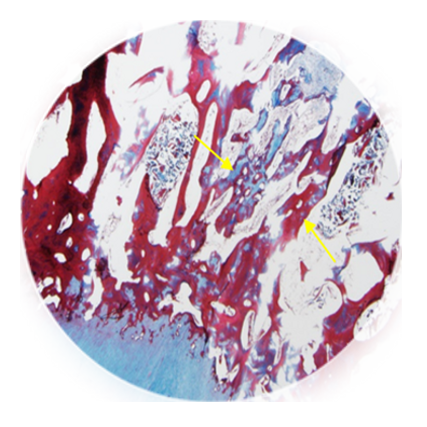

新生编织骨沉积在珊瑚移植物的表面: 观察到毛细血管向CoreBone移植物内生长

临床前动物模型显示:植入6个月实现骨骼与软骨完全再生

层层活跃的骨祖细胞紧密附着于生物活性珊瑚矿质表面(体内移植48小时后观测结果)